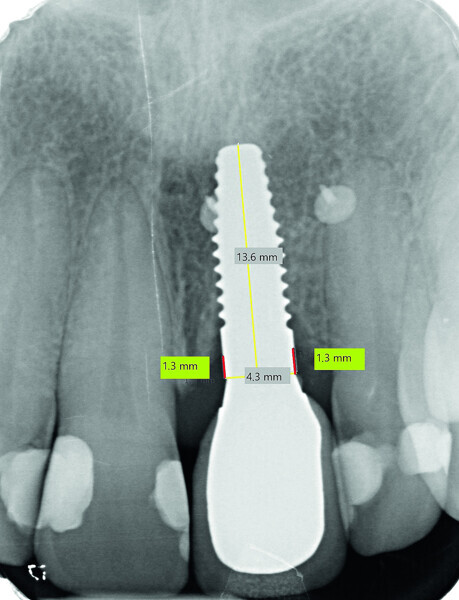

Fig. 13b: Bone resorption was detected after six months and bone gain after 12 months. The yellow line represents the actual implant length (13.6mm). The red lines indicate the mesial and distal distances from the top of the implant to the first bone contact.